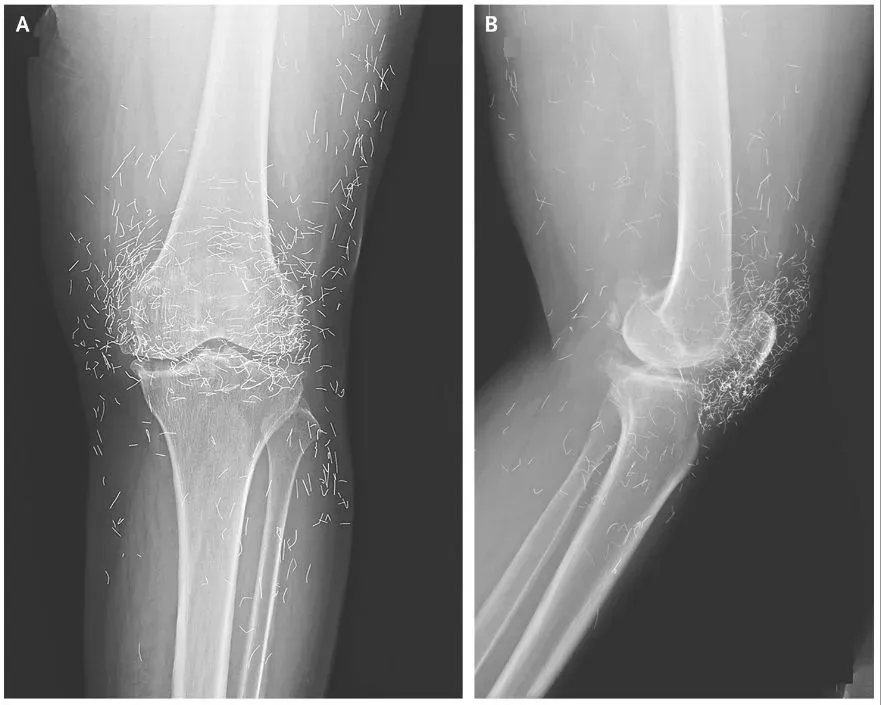

Pihak medis menjelaskan pasien awalnya datang ke rumah sakit dengan keluhan lutut yang terasa sangat nyeri. Setelah dilakukan pemeriksaan lebih lanjut, hasil rontgen menunjukkan adanya perubahan bentuk pada tulang kering bagian dalam lutut yang tampak menebal dan mengeras.

Selain itu, pertumbuhan tulang kecil atau bone spurs juga muncul di sekitar sendi lutut. Pada saat yang sama, dokter melihat adanya bintik-bintik putih dalam jumlah besar yang ternyata merupakan benang emas.

"Ia kemudian datang ke rumah sakit karena lututnya sangat nyeri. Rontgen pada lutut kirinya menunjukkan tulang kering bagian dalam menebal dan mengeras. Ada juga pertumbuhan tulang kecil di sekitar tulang kering dan tulang paha dekat sendi lutut," imbuhnya.

Temuan mencengangkan muncul dalam hasil rontgen berikutnya. Ratusan benang emas terlihat jelas menempel di sekitar sendi lutut.

"Dokter juga melihat ratusan bintik putih pada hasil rontgen di sekitar sendi lutut, yang ternyata adalah benang emas kecil," ungkapnya.